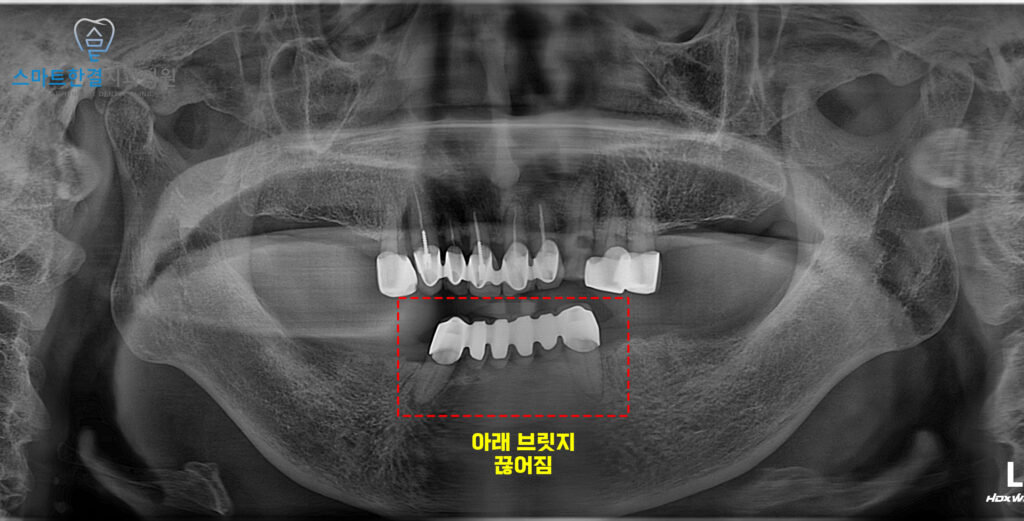

24.04

위 환자분께서는

아래쪽 잔존 브릿지가 끊어져

불편함으로 인해

수원치과 스마트한결에 내원해 주셨는데요.

확인해 보니, 브릿지가 끊어지면서

남아 있는 잔존 지대치 역시

오래된 보철 하중을 견디지 못해

구조적으로 많이 약해진 상태였고,

일부는 치아 균열과 염증 소견까지

동반하고 있었어요.

이로 인해 정상적인 저작이

어려웠을 뿐 아니라,

추가적인 파절이 발생할 가능성도

높은 상황이었는데요.

위쪽도 상태가 안좋았지만

우선은 그대로 쓰면서 유지하고

아래쪽은 전체 발치 후 임플란트를 식립하기로

계획을 수립했어요!